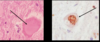

Subarachnoid hemorrhage

Caused by Berry aneurysm

What is this. What are the complications of this?

Berry aneurysm

Rebleeding

Vasospasm

Fibrosis of subarachnoid space